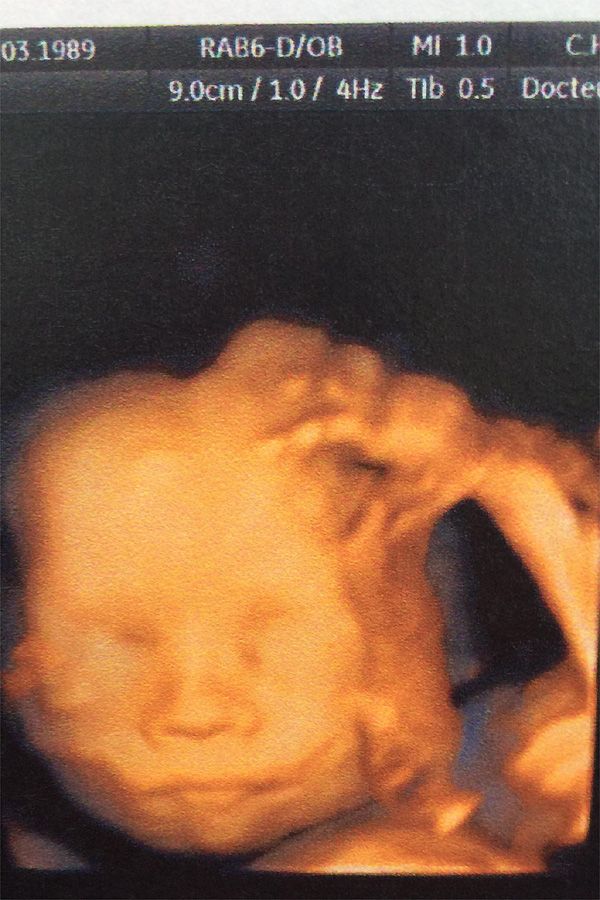

Le bébé de Céline...